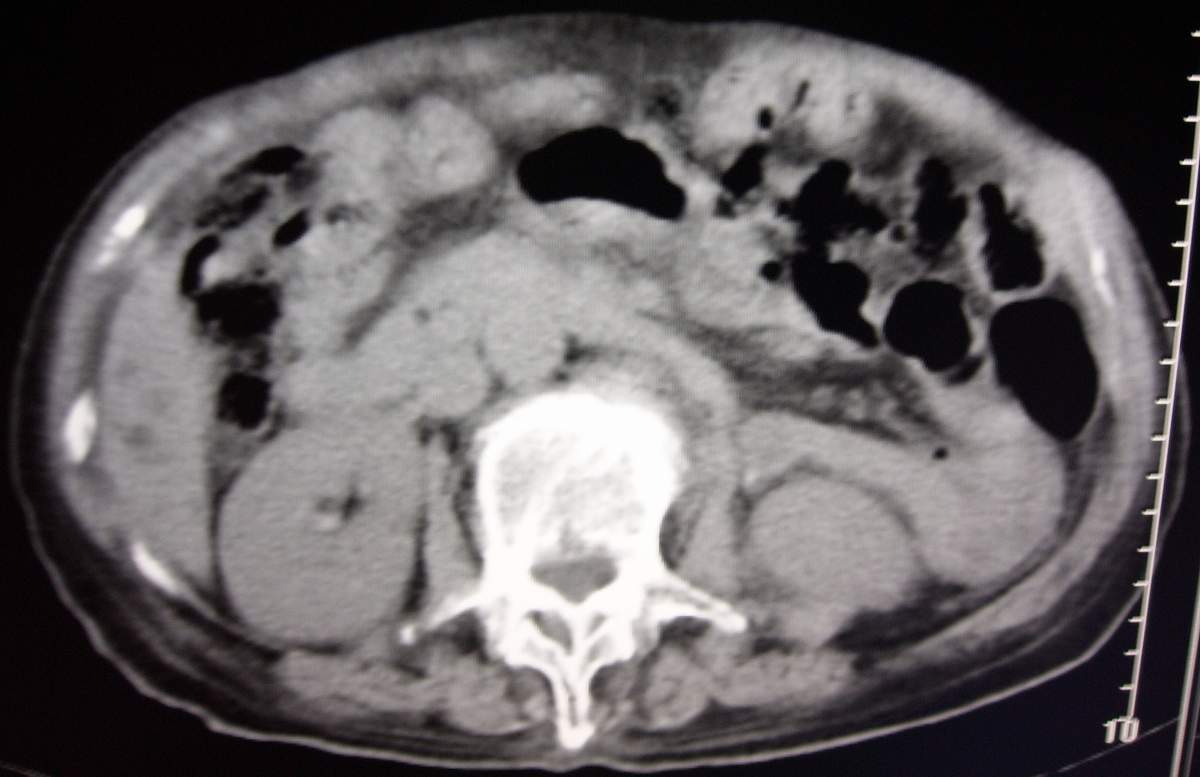

男,77岁,病史不详。

肝内胆管扩张、主胰管扩张 ,胰头影大,考虑胰头癌或胆管下端癌侵犯胰腺可能性大

另外见:胆囊结石 左肾囊肿

肝内外胆管明显扩张,但是程度较轻,应该是个慢性的过程,增强扫描后未见明显异常强化,胰管增宽、扩张考虑为胰头部占位性病变。

慢性胆囊炎,胆结石,左肾囊肿,胰头癌伴肝内胆管、胰管扩张,不除外侵犯肠系膜上静脉的可能。

肝内胆管普遍扩张,呈串珠状改变,走行不规则,且右叶胆管周围肝实质密度呈条片状减低,未见占位性病变,外周胆管及胰管扩张不及肝内胆管.胰腺钩突形态正常,胰十二指肠区域未见明显结节及肿块,初步考虑慢性胆管炎可能性大.请结合临床病史.另外用宽窗看一下吉氏筋膜有无增厚.

1 肝内外胆管扩张,肝内明显,胰管扩张,胰头明显增大,符合胰头癌双管征。2 胆囊壁略增厚,胆囊内可见高密度结石影,胆囊炎、胆结石3 左肾囊肿